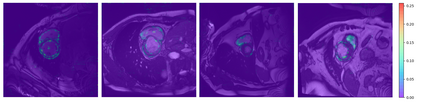

In this paper, we aim to improve the performance of semantic image segmentation in a semi-supervised setting in which training is effectuated with a reduced set of annotated images and additional non-annotated images. We present a method based on an ensemble of deep segmentation models. Each model is trained on a subset of the annotated data, and uses the non-annotated images to exchange information with the other models, similar to co-training. Even if each model learns on the same non-annotated images, diversity is preserved with the use of adversarial samples. Our results show that this ability to simultaneously train models, which exchange knowledge while preserving diversity, leads to state-of-the-art results on two challenging medical image datasets.